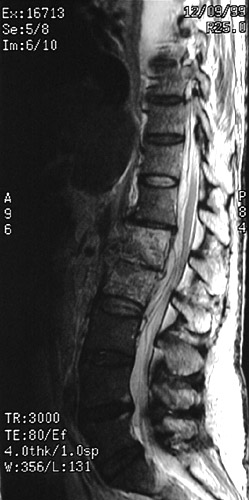

| The sagittal MRI scan view of the lumbar region of the spinal cord above demonstrates a fluid collection not as bright as the normal CSF with the T2 weighted scan, indicative of an epidural abscess. The infection has spread into the adjacent L1-L2 vertebral bodies. With the T1 weighted scan below can be seen the same epidural abscess. |